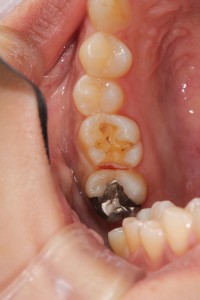

術前術後です。矢印の部分がオールセラミックインレーです。

セラミックインレー

費用11万円

リスクとして歯を削る量が多いため痛みが出る可能性と強い力によって割れる可能性がある。